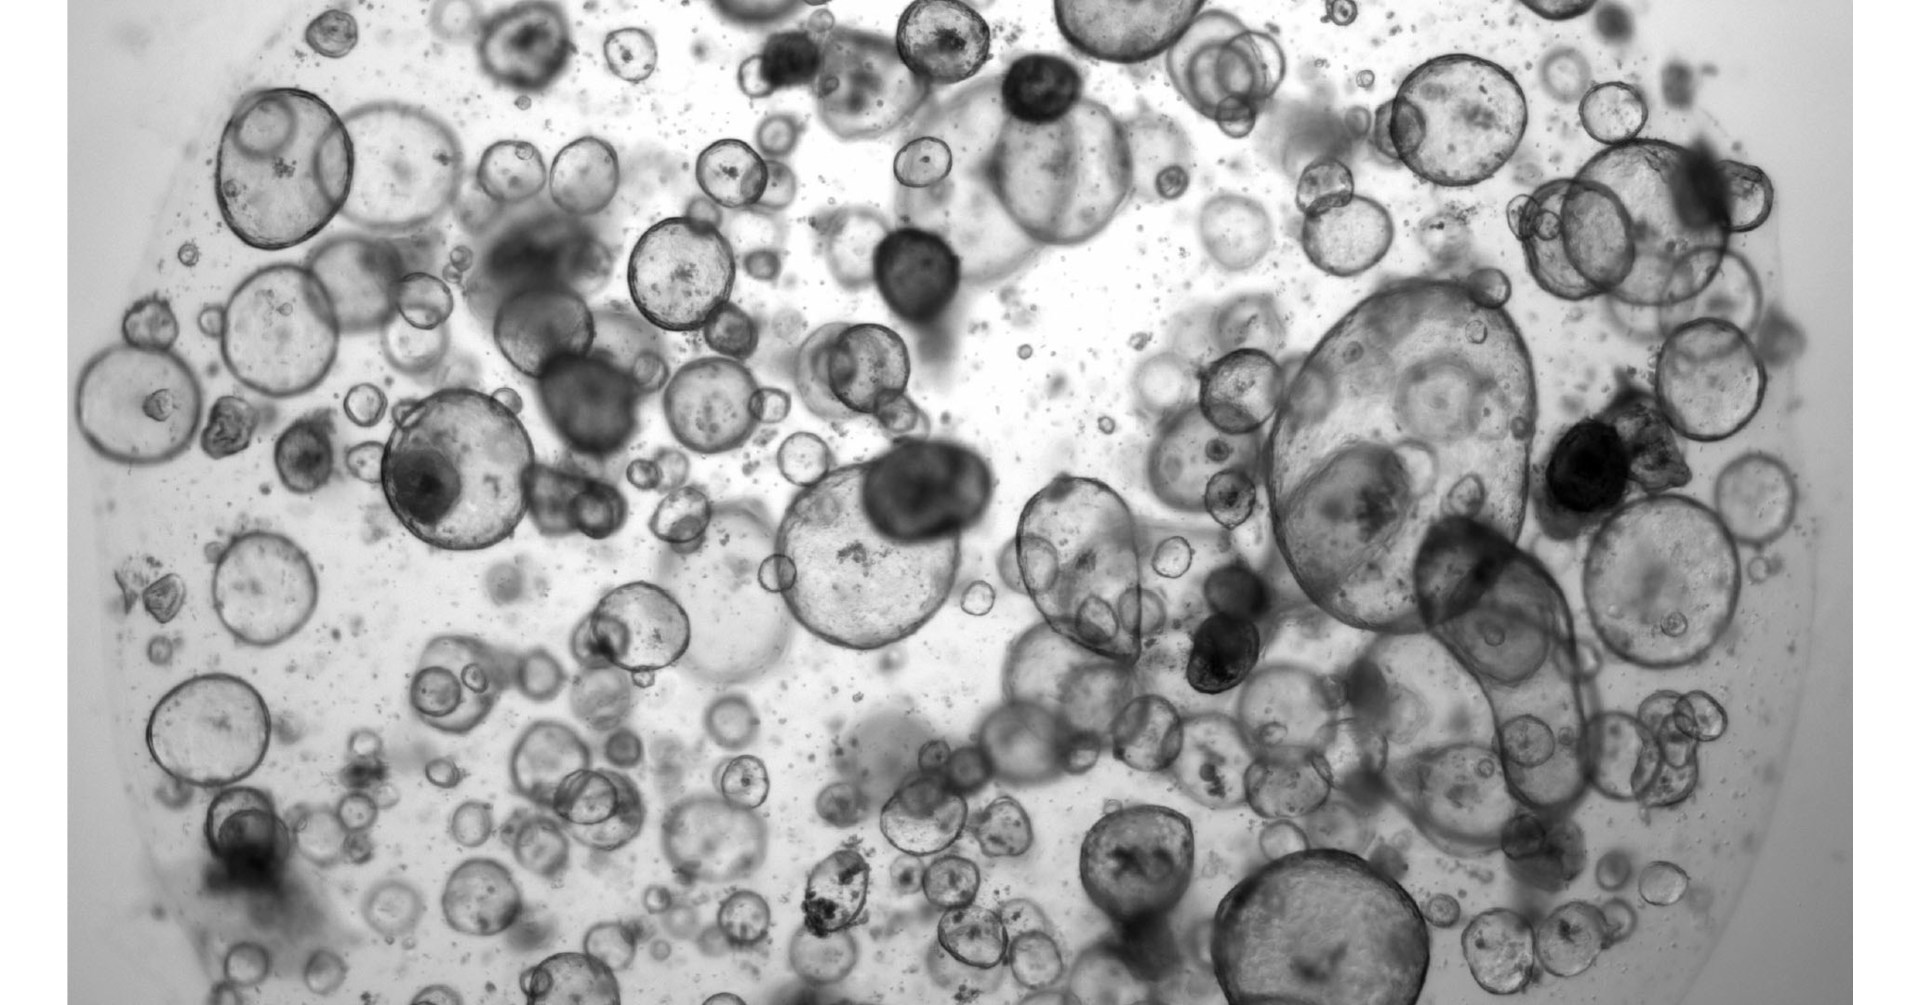

Finally We wish PressBee provided you with enough information of ( How organoids can guide pancreatic cancer therapy )